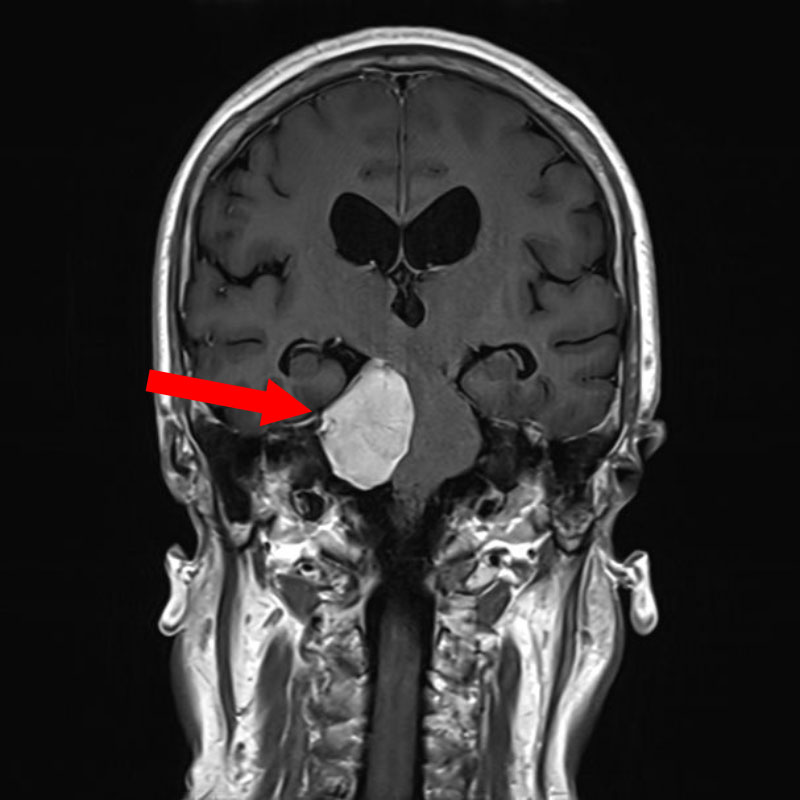

下垂体腺腫

頭蓋内腫瘍摘出術

No.’25_112 手術前1

No.’25_112 手術前2